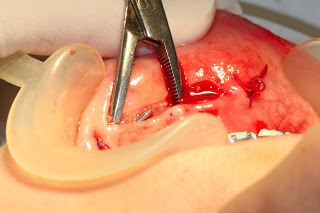

Se firmó consentimiento informado y se programó para cirugía bajo anestesia local. Bajo anestesia local con lidocaina HCl 2% más epinefrina 1:80,000, se realizó una incisión horizontal de aproximadamente 2cm sobre el borde superior del cuerpo extraño.

Se hizo disección por planos con pinzas Mosquito hasta ubicar la barra metálica, la cual fue retirada del labio inferior con la misma pinza. La mucosa oral fue suturada con Vicryl 4-0. Fue prescrita una tableta de 500 mg de amoxicilina cada ocho horas durante seis días. (Figuras 3 y 4).